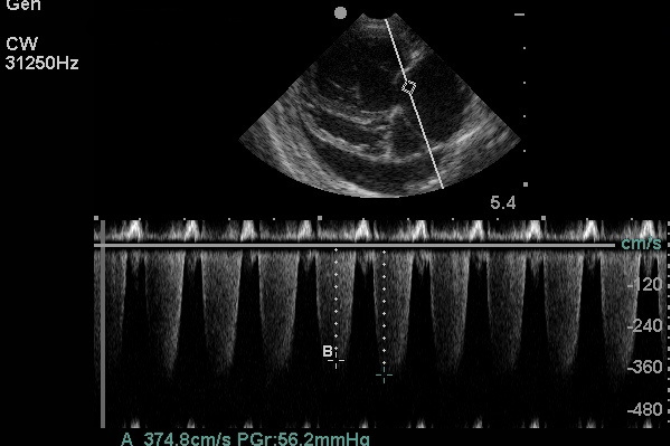

• Assess systolic and diastolic function

• Evaluate valve structure and regurgitation

• Degenerative mitral valve disease